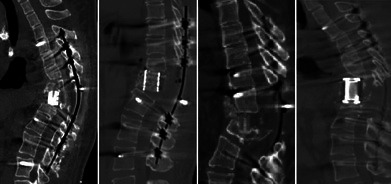

目的:大量研究报道了颈腰椎退行性疾病患者椎间融合器(IFDs)匹配不良的表现及影响因素。然而,目前还没有研究解决在后路脊柱切除术(PVCR)手术中使用ifd匹配的问题。本回顾性影像学研究的目的是分析PVCR后ifd匹配不良的相关危险因素。方法:回顾了2006年6月至2024年7月期间92例PVCR后使用ifd的患者的数据。将ifd植入失败、相邻椎体骨折、沉降大于5mm、角度形成超过10°、错位(定义为超过匹配界面外缘的ifd的三分之一)作为筛选指标,将患者分为匹配不良组和匹配组。通过单因素和多因素logistic回归分析评估匹配不良的潜在危险因素。以受试者工作特征曲线下面积(AUC)评价多元回归模型。结果:92例患者中37例(40.2%)匹配不良。单因素logistic回归分析显示,术前、术后矢状Cobb角、截骨面夹角、置入椎体总数、切除椎体数、ifd高度、钛网或人工椎体的使用是导致匹配不良的潜在危险因素。多因素逐步回归分析显示,术前矢状Cobb角(OR = 1.053, p = 0.001)、截骨面夹角(OR = 1.152, p = 0.003)、ifd高度(OR = 1.058, p = 0.033)是吻合不良的独立危险因素。对于匹配差的情况,该多元回归模型的总体预测性能(AUC = 0.872)令人满意。结论:在PVCR中使用ifd与高的即时匹配不良率相关。术前矢状Cobb角、截骨面夹角、ifd高度是吻合不良的独立危险因素。

Methods: Data from 92 patients using IFDs following PVCR between June 2006 and July 2024 were reviewed. IFDs implantation failure, adjacent vertebral fractures, subsidence greater than 5 mm, angle formation exceeding 10°, and malposition (defined as one-third of the IFDs exceeding the outer edge of the matching interface) were used as screening indicators to divide patients into poor matching and matching groups. Potential risk factors of poor matching were assessed through univariate and multivariate logistic regression analysis. The multiple regression model was evaluated by the area under the receiver operating characteristic curve (AUC).

Results: Among the 92 patients, 37 (40.2%) experienced poor matching. Univariate logistic regression analysis revealed that the preoperative and postoperative sagittal Cobb angles, the angle between osteotomy surfaces, total instrumented vertebrae, the number of vertebrae resected, the height of IFDs, and the use of titanium mesh or artificial vertebral bodies were potential risk factors for poor matching. Backward stepwise multivariate logistic regression analysis indicated that the preoperative sagittal Cobb angle (OR = 1.053, p = 0.001), the angle between osteotomy surfaces (OR = 1.152, p = 0.003), and the height of IFDs (OR = 1.058, p = 0.033) were independent risk factors for poor matching. The overall predictive performance of this multiple regression model (AUC = 0.872) for poor matching was deemed satisfactory.